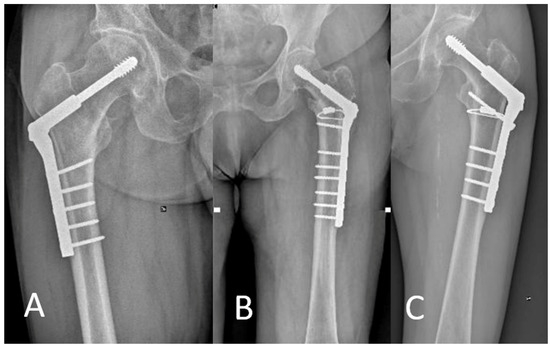

Angle-Adjustable Dynamic Hip Screw Plate for Unstable Trochanteric Fractures in Middle-Aged Patients: Mid-Term Outcomes and Return to Sport

2.1. Surgical Technique